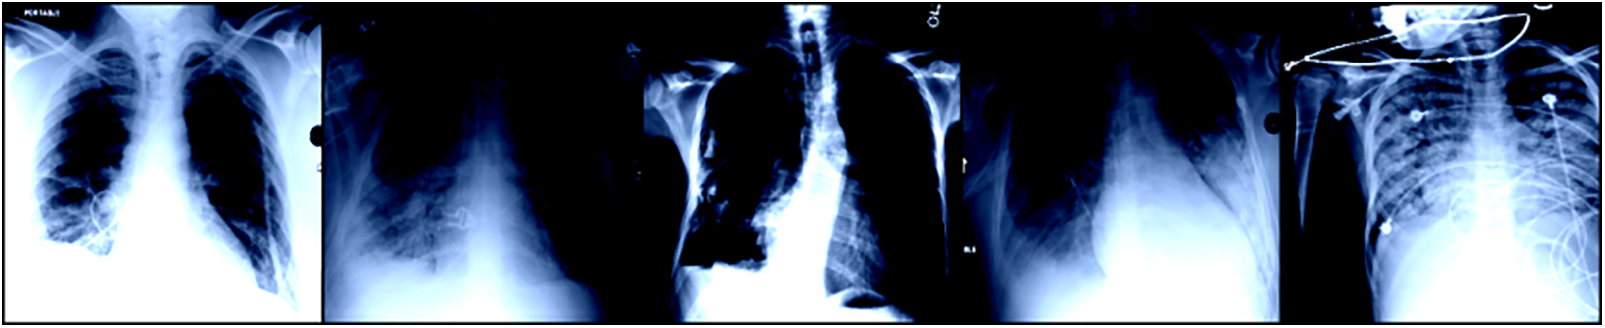

The datasets of coronavirus and TB patients are collected from Kaggle [20]. The tuberculosis dataset is accumulated from an alternate source, and the COVID-19 dataset is gathered from an alternate Kaggle account. There are 357 chest X-ray images for coronavirus patients. These two datasets additionally contain chest x-beam pictures of healthy individuals. After the collection of information from various sources, the data is combined to create a solitary dataset. This dataset contains pictures of coronavirus and tuberculosis patients’ chest x-beams. Additionally, the dataset also contains X-beam images of healthy individuals. The information acquisition layer is shown in Fig. 2. A few X-beam images for tuberculosis and coronavirus patients are presented in Fig. 3.

Figure 3: Sample data from the provided dataset

The information has been designed, resized, and standardized to address these issues. As X-beam images are of various sizes, we resized our pictures to 224 × 224. The obtained pictures are in various organizations. The pictures are in jpg format, png configuration, or other formats. In this way, we converted each of the pictures to png format for further handling. Our X-beam images have various scales. Some pictures are brilliant and some are hazy. Along these lines, we performed picture scaling to standardize our information. The following figure shows a picture after the pre-handling steps. We obtained the five X-beam images as displayed in Fig. 5 during the preprocessing stage.

Figure 5: A few sample images from TB dataset